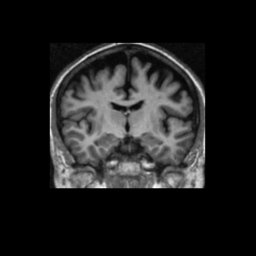

Accuracy is reported as Dice overlaps between a tool's segmentation and the Internet Brain Segmentation Repository (IBSR) manual segmentation for each of the 18 IBSR subjects. The inter-tool comparison (on the left below) shows the median Dice coefficient for each tissue class. The overlaps for FSL (from which the median values are drawn) are shown in the plot on the right.

Subject Accuracy (IBSR)

Overlap coefficients for each tissue class are shown here for each IBSR subject. Select a subject below to see the FSL results compared to other tools.